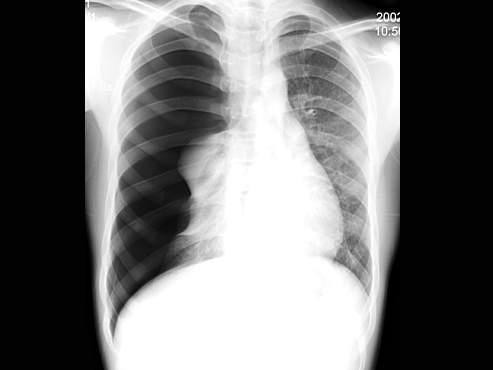

男,16岁,突感呼吸困难,大汗淋漓,胸片检查如图,最可能的诊断是()

• A.右侧肺气肿

• B.右侧肺部肿块

• C.右侧气胸

• D.右侧肺大泡

• E.右侧肺挫伤